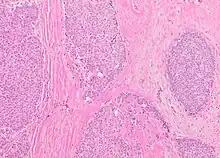

Microscopic histopathological analyses of SPC lesions (refer to adjacent high-power photomicrograph) generally show tumors with multiple circumscribed nodules of expanded ducts filled with neoplastic epithelial cells which may appear spindle-shaped or plasma cell-like, have red to pink cytoplasm due to the uptake of eosin after staining with hematoxilin & eosin, and eccentrically-placed nuclei. Rarely, signet ring-shaped cells are present. The tumors may have cystic and hemorrhagic areas. Myoepithelial cells are found within and at the periphery of these tumors. The papillary architecture seen in the other SCB types is in general not apparent; rather, pseudo-rosettes (i.e. radial arrangements of neoplastic cells around small blood vessel) and nuclear palisading (i.e. parallel arrangements of the nuclei in rows of tumors that resembles picket fences) around stromal cores (i.e. supporting tissues) may be seen. SPC tumor tissues typically (>50% of cases) have areas of neuroendocrine differentiation. The presence of these areas strongly supports the diagnosis of SPC.[21] The signet ring-shaped cells in these tumors contain cytoplasmic mucin-containing vacuoles which push their cells' nuclei to one side.[10] Mucin may also occur outside of cells in these lesions. The presence of signet ring-shaped cells bearing mucin-containing vacuoles with or without extracellular mucin strongly supports the diagnosis of SPC. SPC is considered invasive when the tumor nests have a characteristic jigsaw growth pattern with ragged and irregular margins with the loss of myoepithelial cells at the site(s) of invasion.[21] Rarely, invasive SPC occurs with nearby invasive carcinoma of NST, lobular carcinoma, cribriform carcinoma, or tubular carcinoma breast tumors.[3]